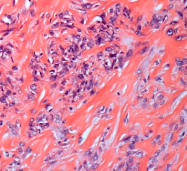

纤维肉瘤

应用机器人导航结合 3D 打印个性化假体治疗小腿黏液纤维肉瘤一例